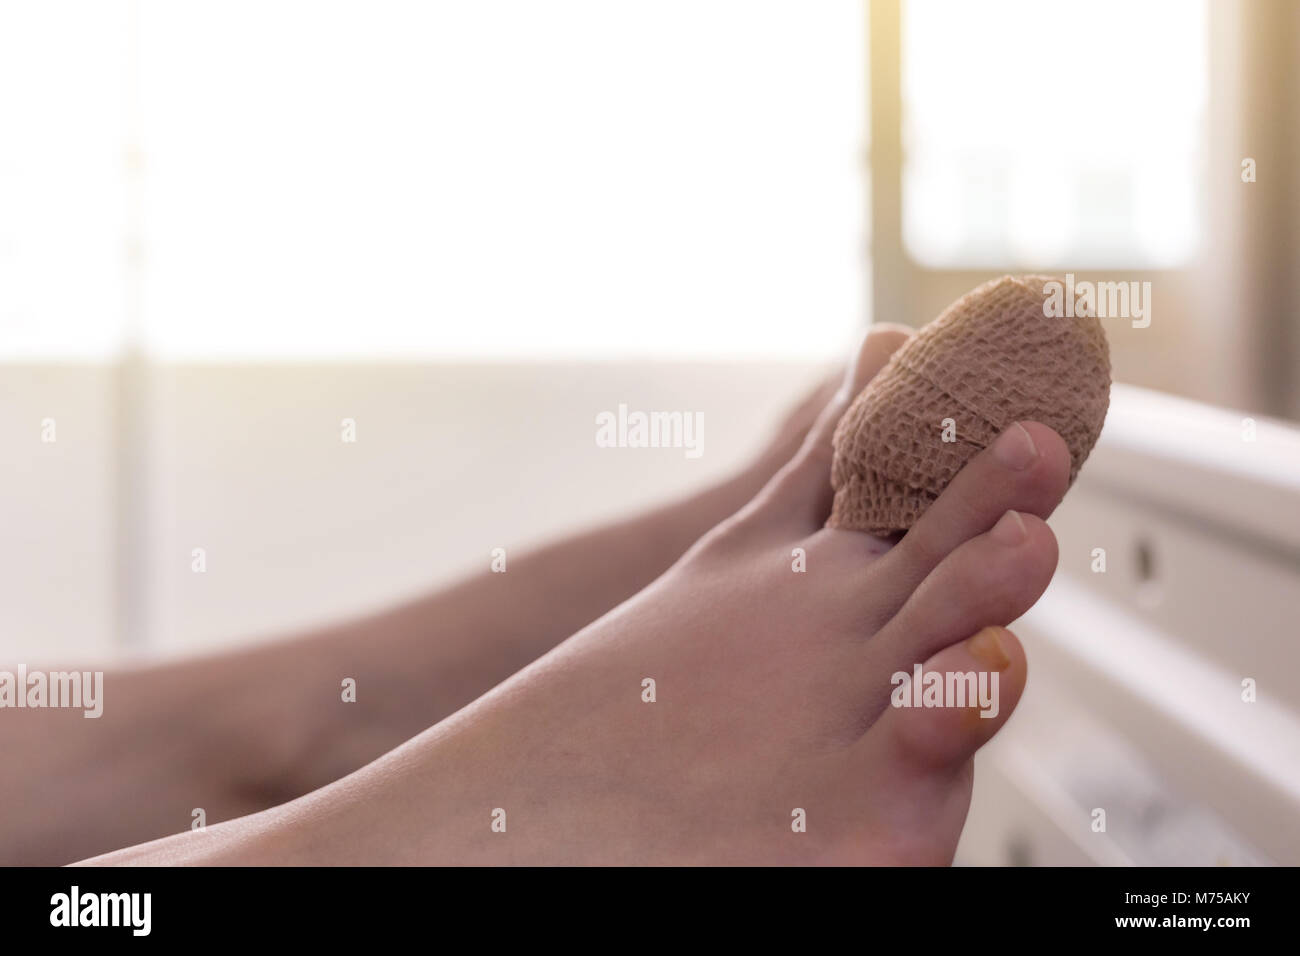

RFM75AJF–Nahaufnahme der Verband index Zehe der weiblichen Patienten schlafen im Bett des Patienten nach einem Unfall

RFM75AKY–Nahaufnahme der Verband index Zehe der weiblichen Patienten schlafen im Bett des Patienten nach einem Unfall mit Sunbeam